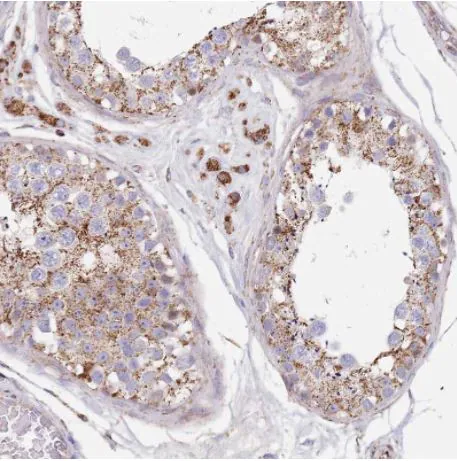

染色定位

细胞膜/质